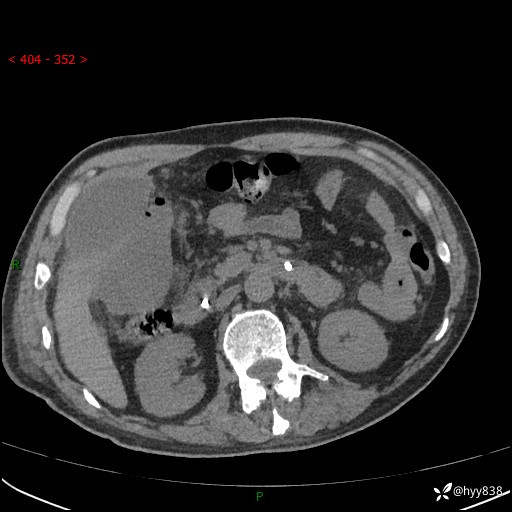

腹部CT平扫

增强